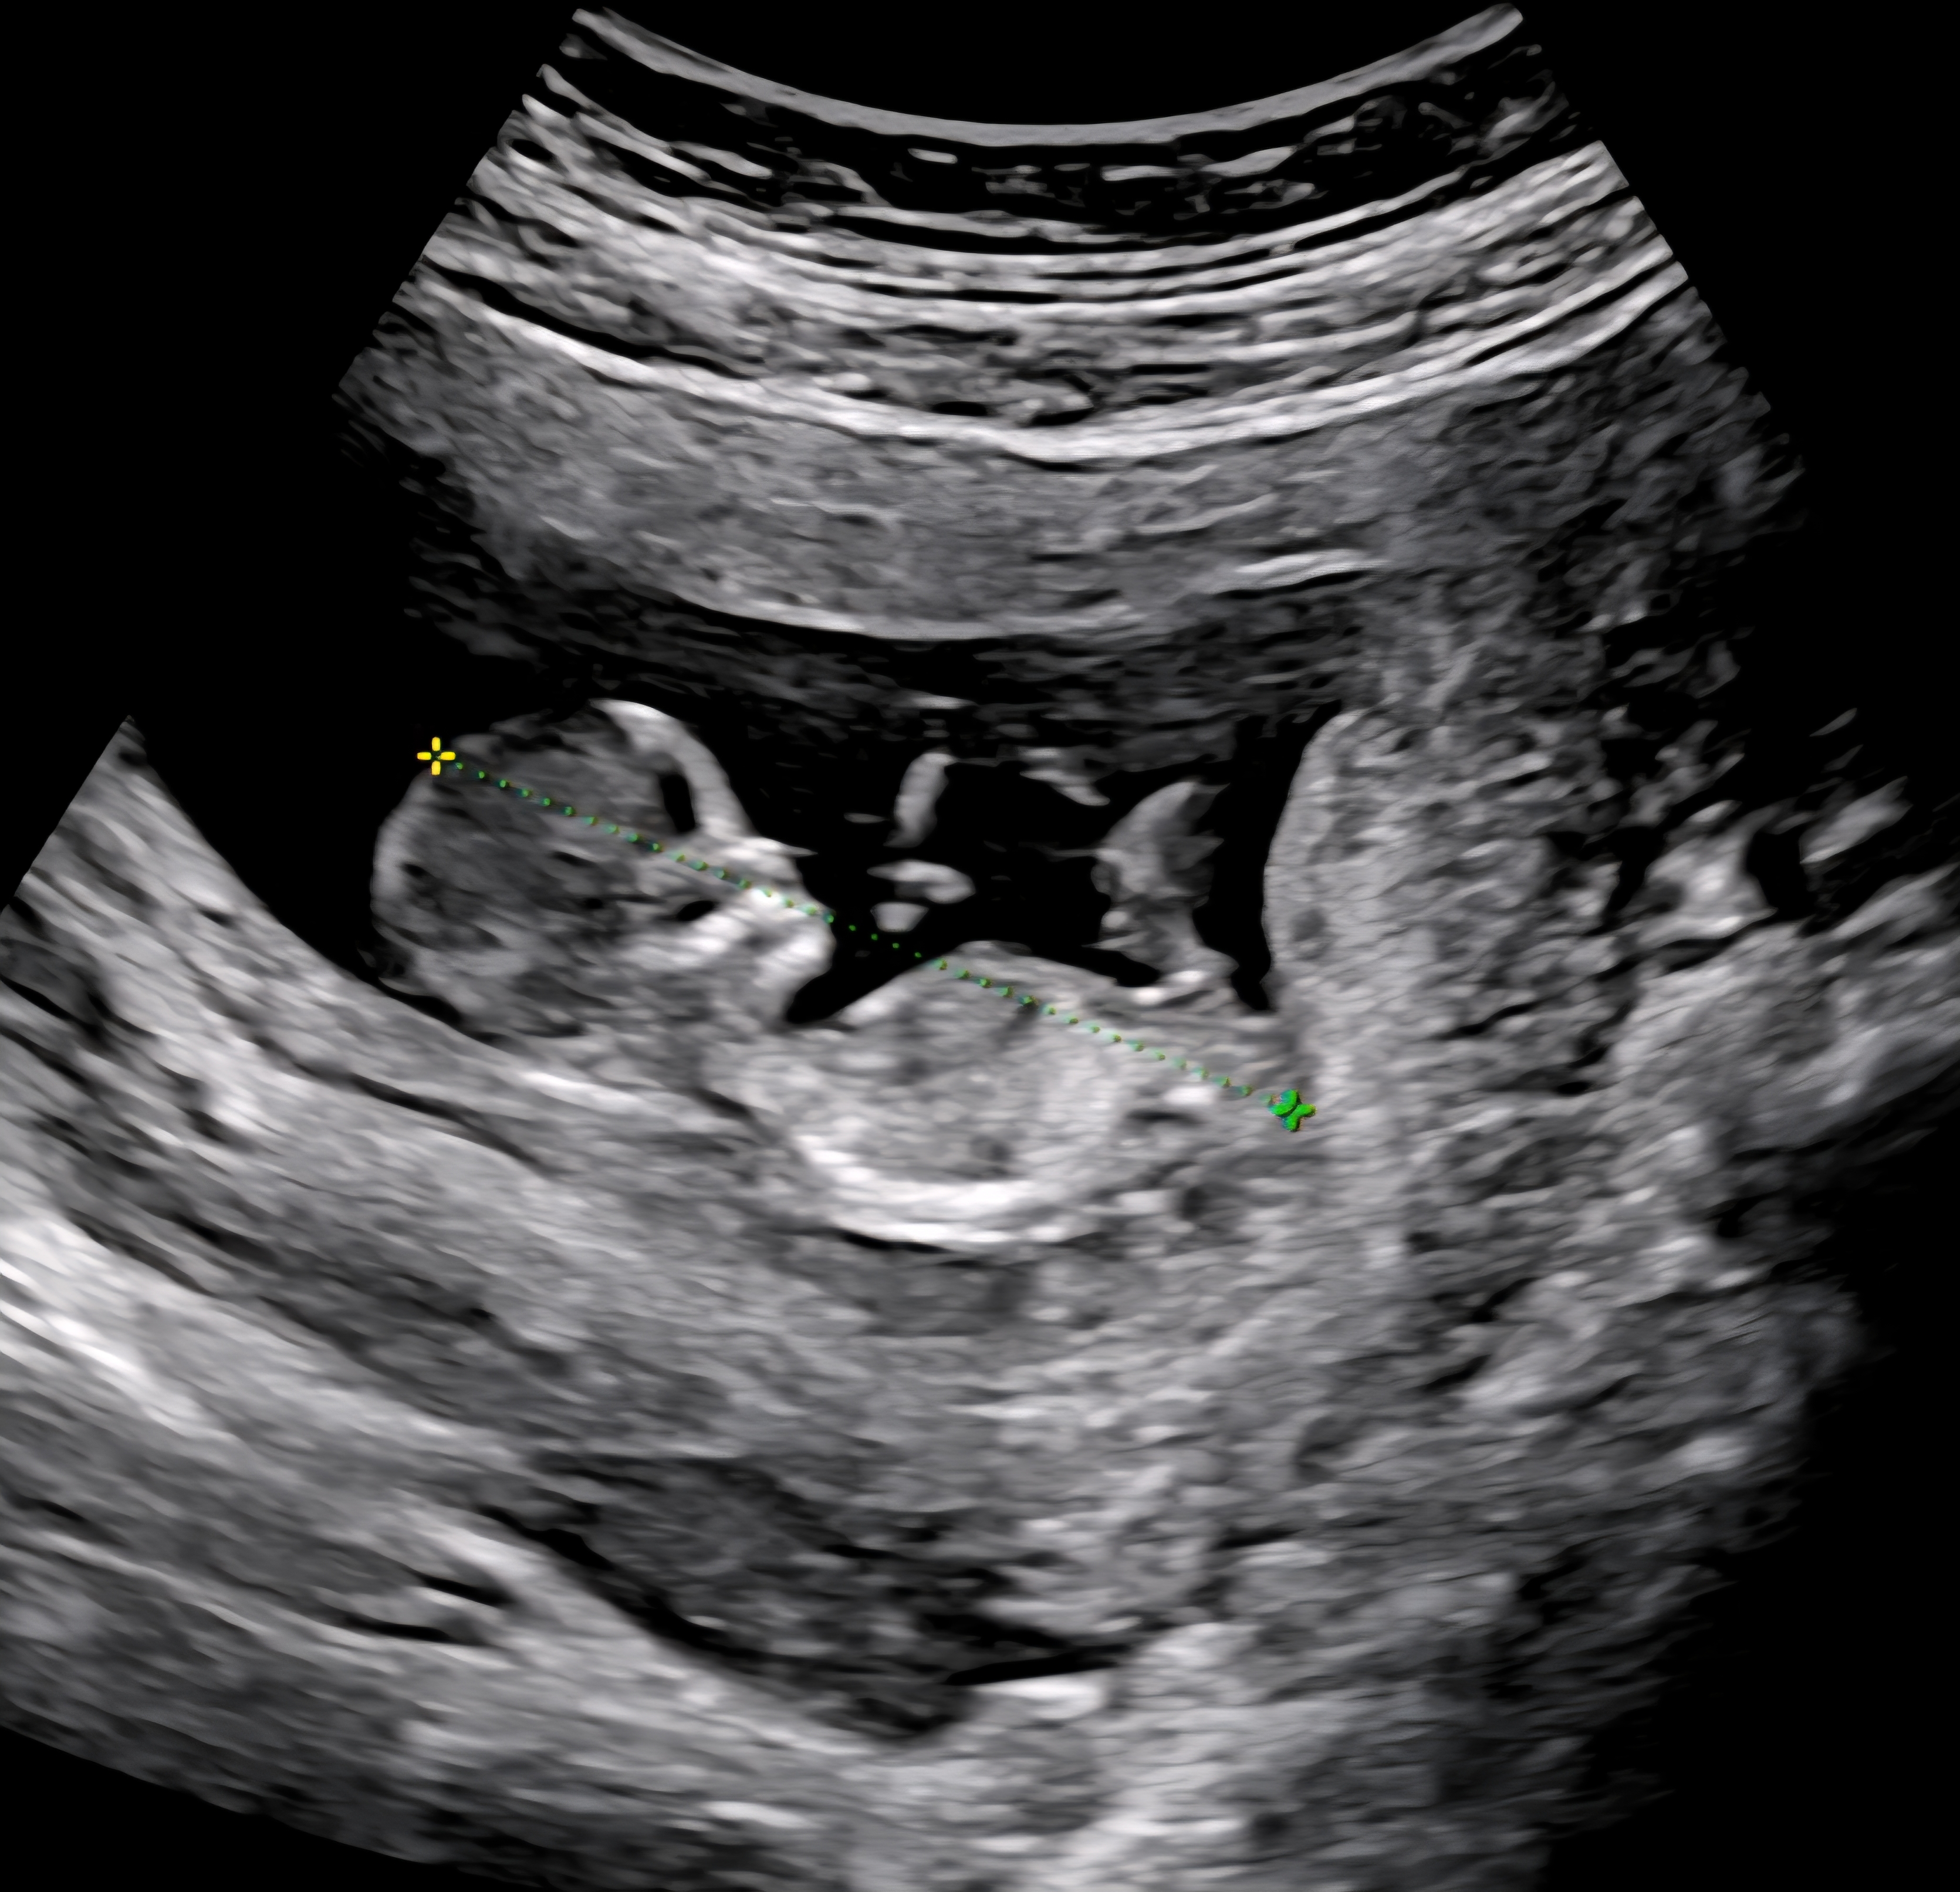

각도법 봐주세요♡베이비빌리/gpt결과다름

베이비빌리는 아들, gpt는 딸이라고 하네요~ 보고 투표해주세요♡